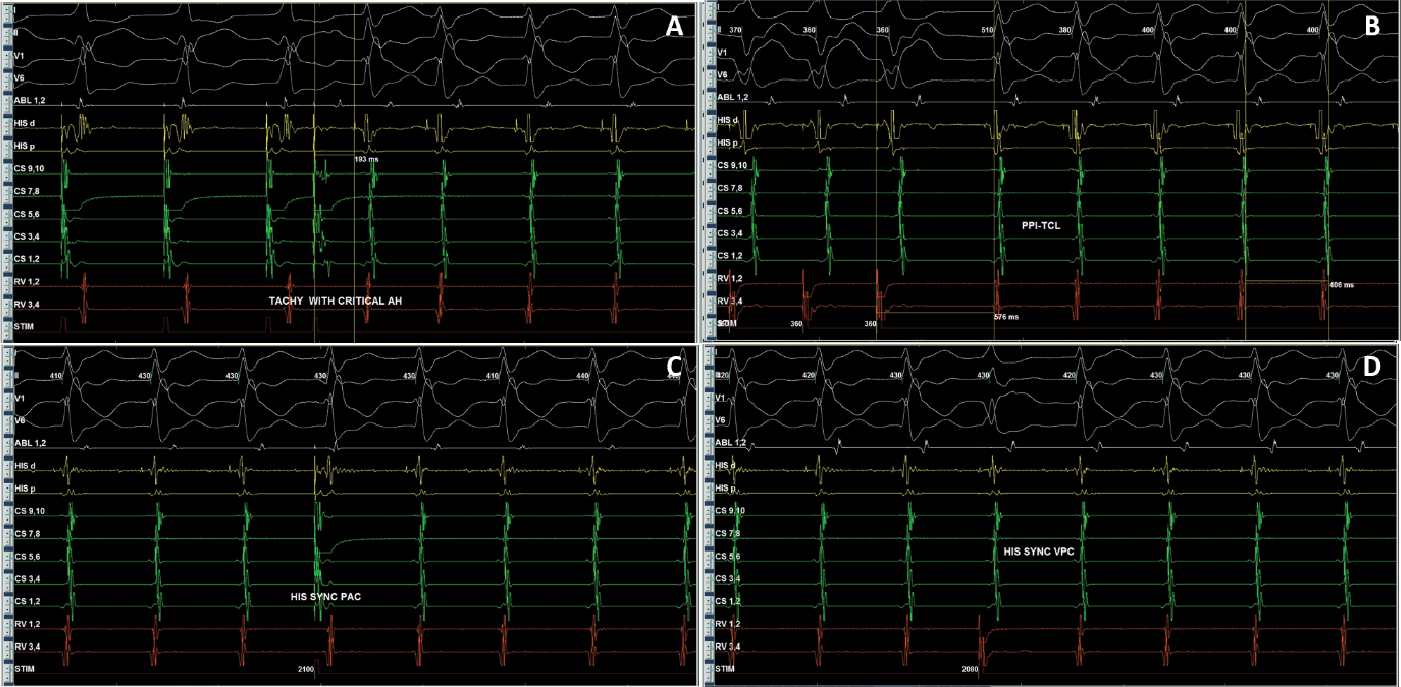

After written informed consent, patient was taken for electrophysiological study. Two quadripolar diagnostic catheters were advanced under fluoroscopy to His bundle region and right ventricular apex. One decapolar catheter was advanced into the coronary sinus. During the electrophysiological study at baseline, atrial-His bundle (AH) and His-ventricular (HV) intervals were 85 ms and 3 ms in sinus rhythm, respectively. There were no atrioventricular (AV) conduction abnormalities. A narrow complex tachycardia (tachycardia cycle length [TCL] = 400 ms) was easily induced during catheter placement with following features: initiation of the tachycardia with a critical AH interval, fixed 1:1 ventriculoatrial (VA) conduction, concentric retrograde activation with VA interval of 37 ms, a post-pacing interval (PPI, 576 ms)–TCL (406 ms) >115 (170 ms) and ventricular overdrive pacing resulted in a VAHV response. His synchronized and early premature ventricular contraction (PVC) did not reset the tachycardia. His synchronized premature atrial contraction (PAC) also failed to reset the tachycardia. The tachycardia was reproducible and consistent (Fig. 2). After confirming the diagnosis of typical AV nodal re-entrant tachycardia (AVNRT) a decision was taken for slow pathway ablation. Using a steerable ablation catheter, with the help of intracardiac electrograms (EGMs) and using fluoroscopy, the region of the slow pathway was identified. Radiofrequency applications were made in the region of the slow pathway while constantly monitoring temperature, impedance, ECG and intracardiac EGMs, monitoring for fast junctional conduction and radiofrequency energy was halted if there was evidence of VA block. Radiofrequency ablation resulted in a junctional rhythm with intact AV conduction, which is a typical response. The AV nodal slow pathway was successfully modified (Fig. 3).

Figure 2. Intracardiac EGMs showing tachycardia induction with AH jump (A), RV overdrive pacing (B), and response of His synchronous PVCs (C) and PACs (D) diagnostic of typical slow-fast AVNRT.